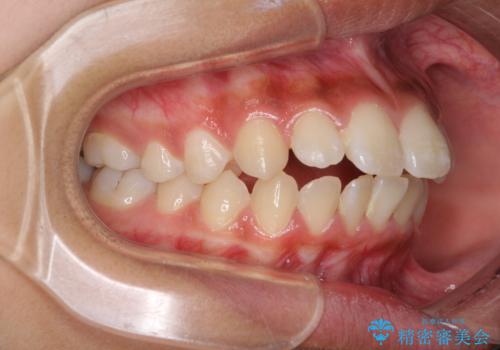

くちばしのように突出した前歯 口元を下げる抜歯矯正

- 上下の出っ歯を気にして来院された患者様です。

口元を積極的に引っ込めるために、上下左右の第一小臼歯を4本抜歯することとしました。

前歯部の突出と開咬は、舌突出癖によるものでしたので、舌のトレーニングをしっかりと行っていただき、1年半程度と短期間で治療を終えることができました。